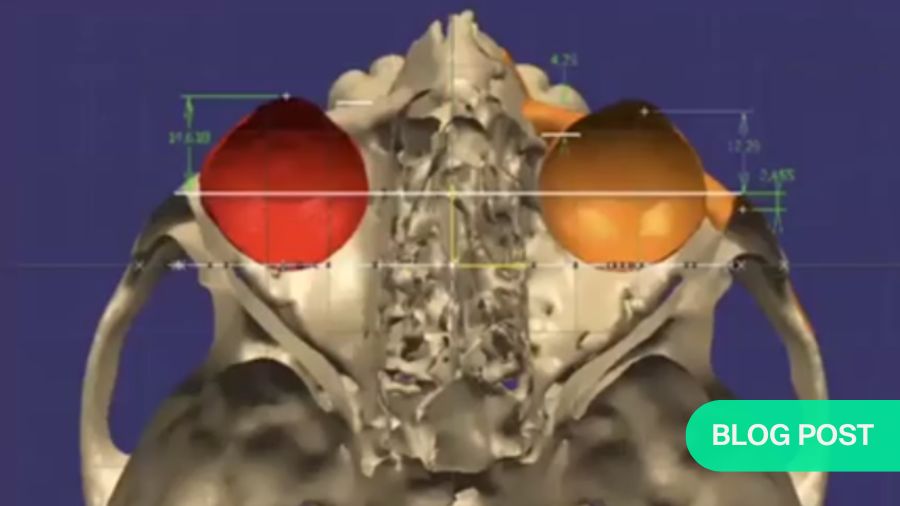

Patient-matched implants can also be used in young patients to correct diplopia occurring because of facial trauma. A young patient sustained a zygomatic injury which developed into enophthalmos with a slight facial defect. As a result, the patient also developed diplopia, which can be challenging to correct in the long term. The initial 3D cephalometric image revealed that the right orbit was lower and more inferior than the left orbit. With the use of 3D simulation, a treatment plan was created which involved repositioning the globe of the eye, placing an implant in the orbit with the correct volume and in the correct position to support the globe, and placing a patient-matched implant to augment the right zygoma. At five years post-surgery, the diplopia was corrected, and the patient had a good esthetic outcome.